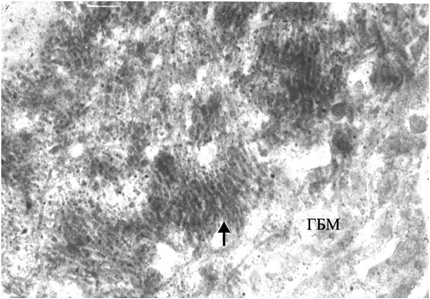

При электронной микроскопии (ЭМ) характерны наличие неравномерной пролиферации, набухание МК и ЭК, инфильтрация капилляров ПЯЛ, расширение мезангиальной зоны и увеличение мезангиального матрикса (ММ), наличие крупных электронно-плотных субэндотелиальных депозитов, реже — мезангиальных. Отличительной чертой является вовлечение в патологический процесс подоцитов — слияние малых отростков подоцитов (МОП), оголение ГБМ, активация подоцитов, повреждение их с появлением жировых, белковых вакуолей, вторичных лизосом и с микровиллезной трансформацией цитоплазмы [2]. В части наблюдений выявляются субэпителиальные депозиты (тубулоретикулярные включения) в виде негомогенных отложений электронно-плотного материала с чередующимися темными и светлыми линиями — «пальцеподобные» («fingerprint») депозиты II типа (рис. 2). Эти включения состоят из рибонуклеопротеина и мембраны, их синтез стимулируется α-интерфероном [45]. Единственными другими обстоятельствами, в которых эти образования могут также встречаться, являются ВИЧ-нефропатия (связанная с хронически высокими уровнями циркулирующего α-интерферона) и лечение α-интерфероном. Тем не менее пациенты с ВИЧ-нефропатией обычно имеют коллабирующий фокальный сегментарный гломерулосклероз, а не пролиферативный ГН с иммунокомплексными депозитами.

Рис. 2. IV класс ВГН. Субэндотелиальные «пальцеподобные» («fingerprint») депозиты. ЭМ. ×15 000